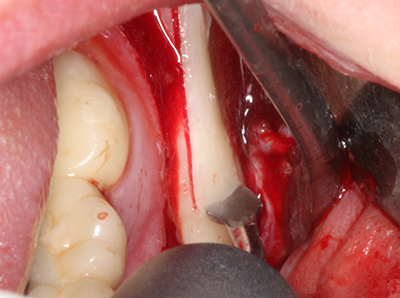

La piezochirurgia presenta altri vantaggi per quanto riguarda la raccolta di blocchi ossei. Oltre all'elevata precisione dell'osteotomia appena descritta, l'utilizzo di puntine per sega molto sottili permette di minimizzare in maniera significativa la perdita di materiale. È molto probabile che si verifichi una maggiore perdita di materiale durante la raccolta utilizzando puntine di strumenti più spessi, in particolare delle frese Lindemann (Lakshmiganthan, Gokulanathan et al. 2012). La separazione basale, necessaria in particolare per i trapianti di blocchi nella zona retromolare, viene semplificata grazie a seghe specificatamente progettate di forma rettangolare; di conseguenza la piezochirurgia è considerata una procedura precisa, semplice e sicura per la raccolta di blocchi di osso nella zona retromolare (Happe 2007) (figg. 1-12).